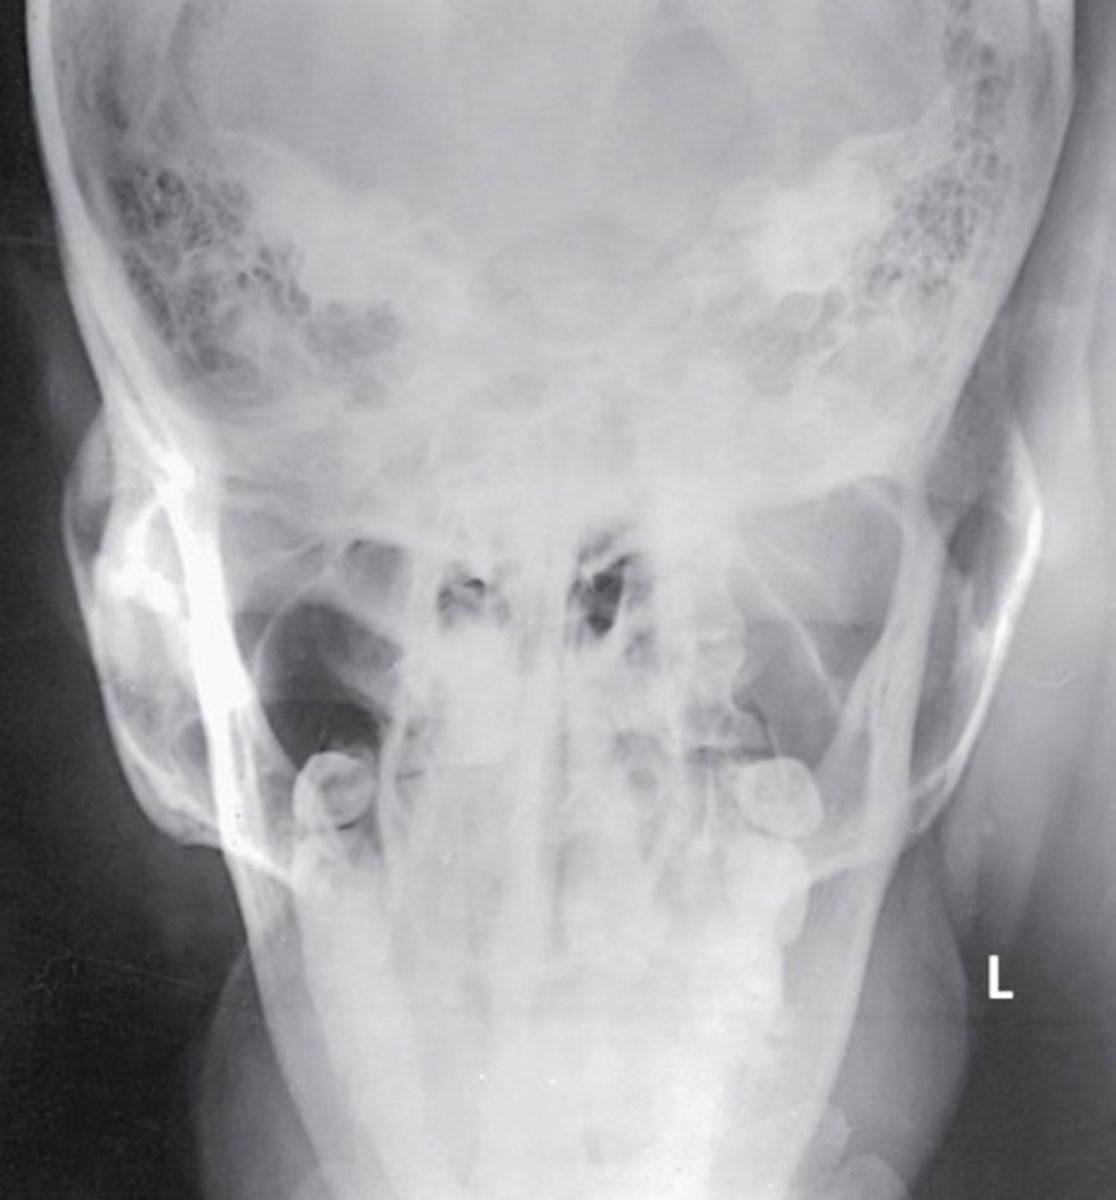

What projection and anatomy is demonstrated in the image below?

SMV of the zygomatic arches